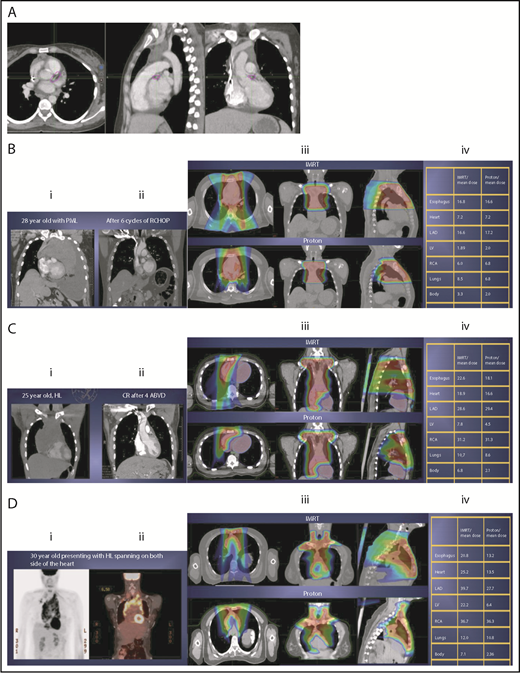

Three scenarios of the relation between mediastinal disease and the heart. (A) Showing how to use the takeoff of the left main stem coronary artery (outlined in pink) to determine the upper and lower mediastinal locations. (B) Scenario 1: coronal CT images of a 28-year-old man with primary mediastinal lymphoma before (i) and after (ii) 6 cycles of rituximab, cyclophosphamide, doxorubicin, vincristine, prednisone (RCHOP) chemotherapy presenting for consolidation with radiation. (Biii) Axial, coronal, and sagittal views of an IMRT plan (upper panels) and a proton plan (lower panels). (Biv) Corresponding mean doses to critical structures using IMRT vs protons. (C) Scenario 2: coronal CT images of a 25-year-old man with Hodgkin lymphoma before (i) and after (ii) 4 cycles of doxorubicin, bleomycin, vinblastine, and dacarbazine (ABVD) chemotherapy presenting for consolidation with radiation. (Ciii) Axial, coronal, and sagittal views of an IMRT plan (upper panels) and a proton plan (lower panels). (Civ) Corresponding mean doses to critical structures using IMRT vs protons. (D) Scenario 3: coronal CT images of a 30-year-old man with recurrent Hodgkin lymphoma as shown in the coronal images of a PET/CT scan (i-ii) presenting for definitive radiation. (Diii) Axial, coronal, and sagittal views of an IMRT plan (upper panels) and a proton plan (lower panels). (Div) Corresponding mean doses to critical structures using IMRT vs protons.

The take-off of the left main stem coronary artery is used to define whether the target is above or below the heart (Figure 2A). In this example (Figure 2B), the exposure of the heart is quite comparable, regardless of which technique is used. Differences in DVHs, as well as the mean dose to other structures, are similar to the proton and IMRT plans.

Scenario 2: target spans the right side of the heart

For the targets on the right side of the heart, IMRT often provide comparable doses to the heart and other structures as proton therapy. Notably, however, even when proton plans give a dosimetric advantage over IMRT plans, the magnitude of advantage could vary between cases, and it needs to be judged individually. For example, for the patient shown in Figure 2C, the mean doses to critical structures from proton therapy are sufficiently lower than those from IMRT to suggest that proton therapy may be preferred because of the large volume spanning the right side of the heart. This example illustrates the need for careful consideration of individual cases before deciding on treatment.

Scenario 3: target is on both sides of the heart

Disease that spans significantly in front of the heart anteriorly, posteriorly, or to the left side poses a particular challenge for IMRT; therefore, proton therapy may be the superior plan. Notably, toxicity to the heart and lungs is not eliminated by using proton therapy; rather, the dose to the heart may be lower than IMRT. Thus, for cases like in Figure 2D, clinicians should carefully weigh the therapeutic benefit against the long-term risks for radiation-induced treatment toxicities before deciding on which technique should be used. Indeed, in this case, proton therapy can significantly avoid the heart and should be sought in an attempt to reduce the dose to the heart substructures.